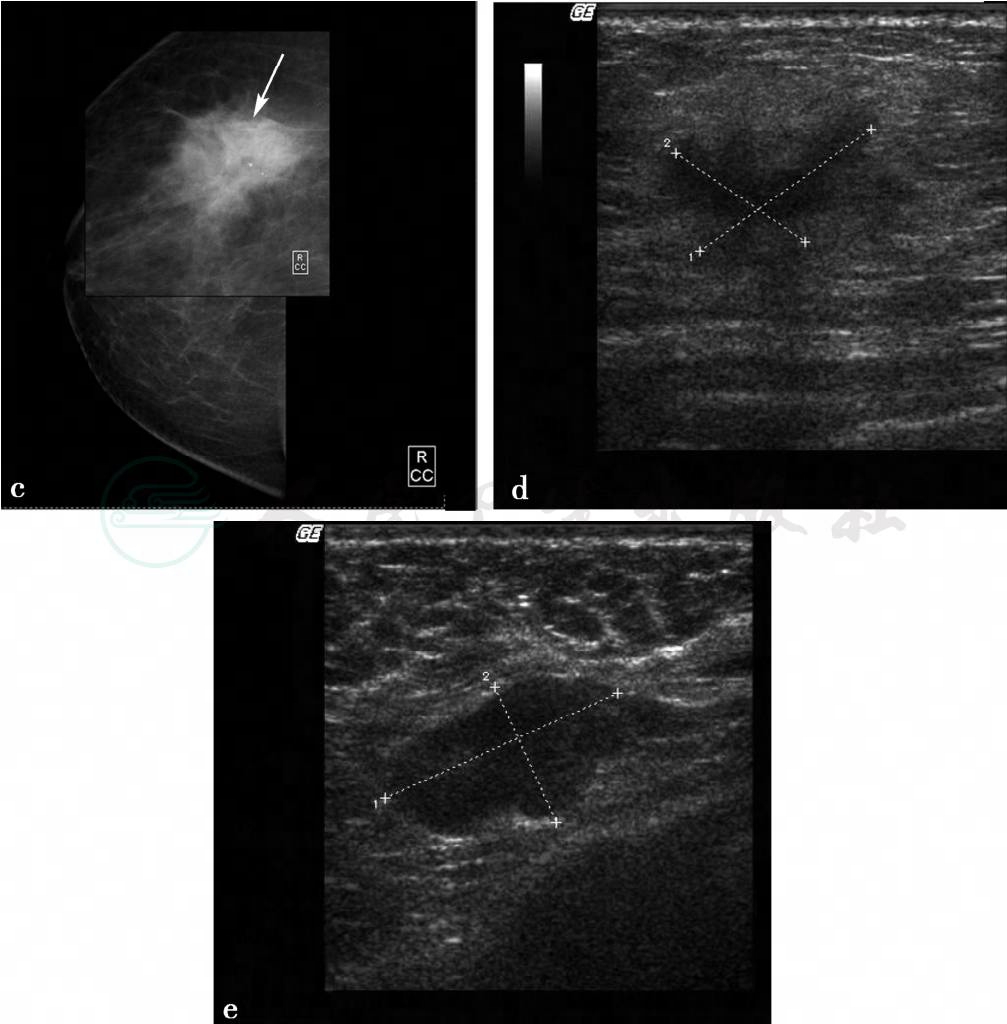

X线及超声检查。

图3 图3a,右乳X线头尾位。图3b,右乳X线内外斜位。图3c,右乳病变局部放大片。X线显示右乳呈脂肪型乳腺,右乳外上不规则分叶状肿物(图箭头所示),大小约1.8cm× 2.3cm,边缘呈蟹足状浸润,其内可见2枚点状钙化,皮下脂肪层清晰,皮肤及乳头正常。图3d,右乳病变二维超声图,超声显示右乳外上1.5cm×2.0cm低回声反射区,形状不规则,边界不清楚,边缘呈蟹足状浸润,内部回声不均匀,肿物后方可见声影。图3e,右腋下淋巴结二维超声图,右腋下可见1.3cm× 2.3cm肿大淋巴结,正常淋巴结门结构消失